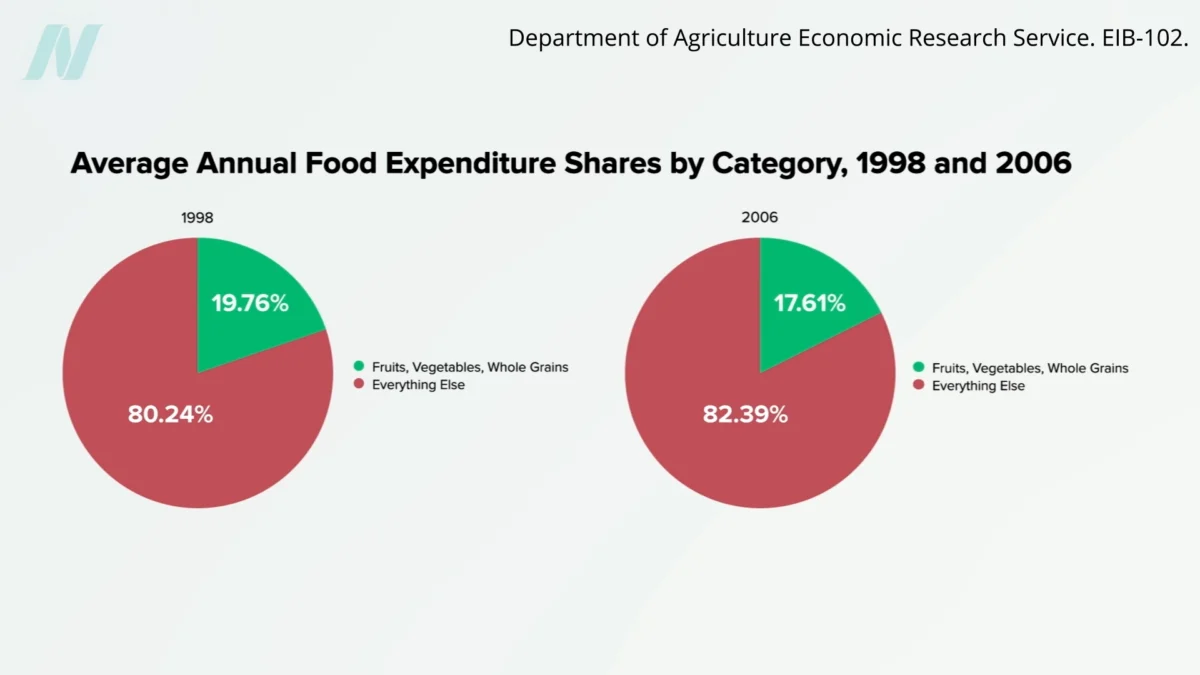

Onions: Unpacking the Evidence from Randomized Human Trials for Health Benefits

Onions, a staple in kitchens worldwide and a cornerstone of countless culinary traditions, have long been lauded for their potential health-promoting properties. While anecdotal evidence and traditional medicine have often…